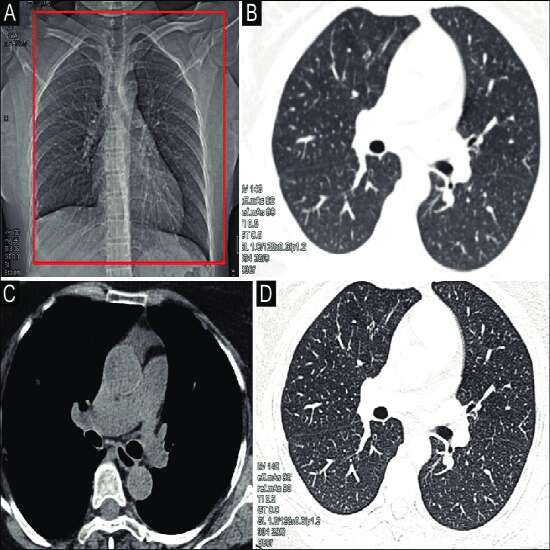

NCCT chest (Non-Contrast Computed Tomography) is a diagnostic imaging technique to detect the chest area. It helps to evaluate the thorax, rib cage, lungs, heart, spinal cord or any other surrounding tissues and muscles This test is usually recommended by the doctor after they have found abnormalities in a plain chest X-ray. Normal chest NCCT scans use low radiation and resolution. Here, the non-contrast is indicated by the word “plain”.

Thin slices of the chest are created from the images, which are taken at different angles and points on the chest.

These pictures are used to create a 3-D image of the chest in the computer system, which can then be printed or sent to the radiologist as a digital file for analysis.